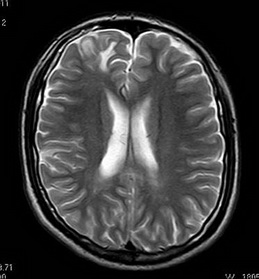

经吴杰主任及其团队详细术前评估后,钟先生接受了右侧额叶癫痫灶切除术,术后至今没有出现癫痫发作。术后病理示:脑软化灶。

术后MR